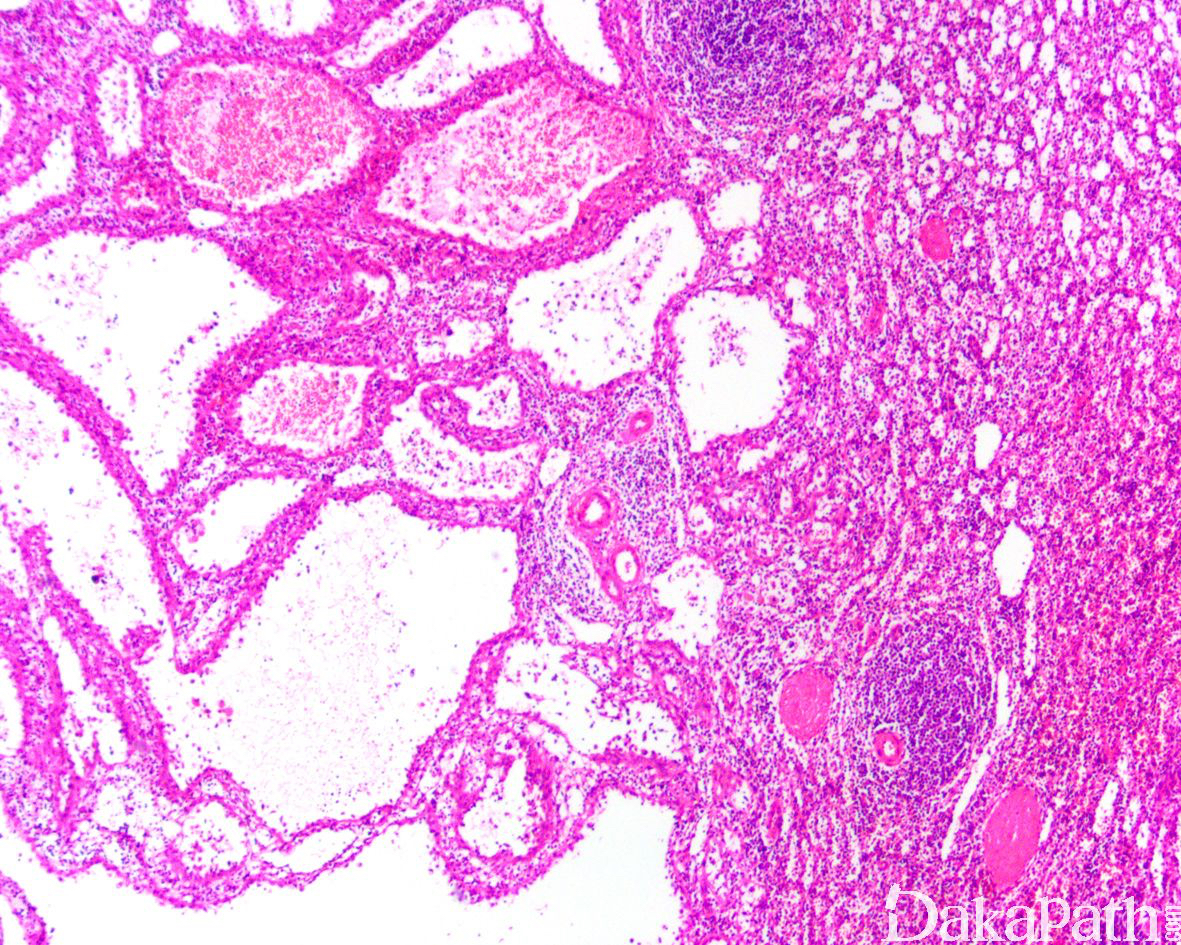

- 可发生于任何年龄,部分可伴发内脏器官的恶性肿瘤;大体上常呈多发或单发的结节状,界限清楚,位于脾脏红髓;

- 结节大小不一,由形态一致的血管互相吻合成网状,似脾窦;

- 血管腔不规则,部分囊状扩张伴突向血管腔的具纤维性间质轴心的乳头结构,其表面衬覆单层内皮细胞;